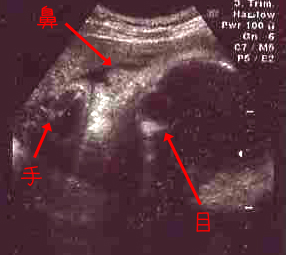

今回は横顔を見せてくれました。

<クリックで拡大>

口の前に手を持っていって女の子らしいポーズ♪

気のせいか、私よりパグ夫くんに似ているような。

32W1D

★頭の大きさ(横幅)8.58センチ

★体重 2091グラム